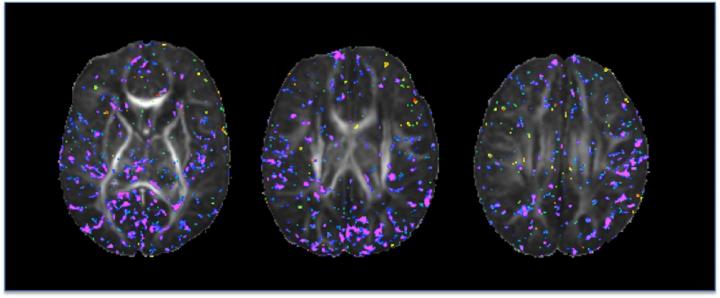

In this study, the researchers looked at the organization of newborn brain tissue using Diffusion Tensor Imaging (DTI), a magnetic resonance imaging (MRI) technique. The DTI images - taken at an average of 20 days after birth-- were used to associate maternal iron intake during pregnancy to differences in cortical gray matter and, to a lesser extent, in major axonal pathways within the underlying white matter of the brain.

The scientists found that maternal iron intake correlated inversely with fractional anisotropy (FA) - a unit of measurement in DTI that is a useful measurement of tissue organization in the brain--at locations scattered throughout the gray matter of the brain. This suggests that higher dietary iron intake is associated with greater complexity and therefore greater maturity of cortical gray matter and, conversely, that lower dietary iron is associated with lesser complexity and more immaturity of the developing gray matter shortly after birth.

"These findings are consistent with our expectations," said Peterson, who is also a professor of professor of pediatrics and psychiatry at Keck School of Medicine of the University of Southern California. "Neurons become increasingly more complex in their extensions and connections as the brain matures, and the maturational delays reported previously in animal models and human behavioral studies of iron deficiency would predict that lower iron intake would produce neurons in cortical gray matter that are structurally less complex and more immature. That is what our DTI findings suggest is the case.'"